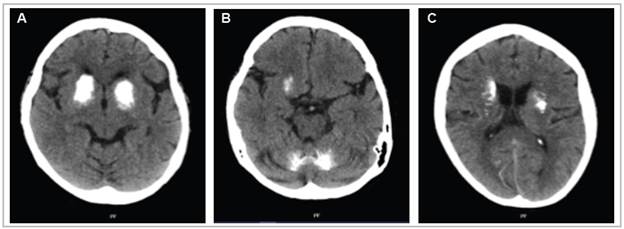

A simple head tomography showed signs of mild cortical atrophy. There were bilateral ring-shaped hyperdensities with irregular borders in the brain stem, basal ganglia and lateral ventricles, involving the cerebellar cortex, especially of the left hemisphere, the head of the caudate nucleus, the internal capsule and the lentiform nucleus, predominantly in the right hemisphere (Figure 1). Symptom management was started with oral haloperidol at 2.5 mg every eight hours and the oral hypoglycemics were deferred, achieving blood glucose control. Calcium and thyroid homeostasis tests were ordered to rule out an organic cause, finding normal vitamin D, ionized calcium, phosphorus, magnesium, thyroid stimulating hormone (TSH) and parathyroid hormone (PTH) levels; free thyroxine (fT4): 1.14 ng/dL; TSH: 1.772 IU/mL; ionized calcium: 1.17 mmol/L; 25-hydroxy vitamin D: 47.6 ng/mL; phosphorus: 3.71 mg/dL; magnesium: 2.03 mg/dL; and PTH: 37.7 pg/mL. Due to persistent symptoms during her hospital stay, the initial dose was adjusted to 5 mg in the morning and 2.5 mg at night, with an adequate clinical response.